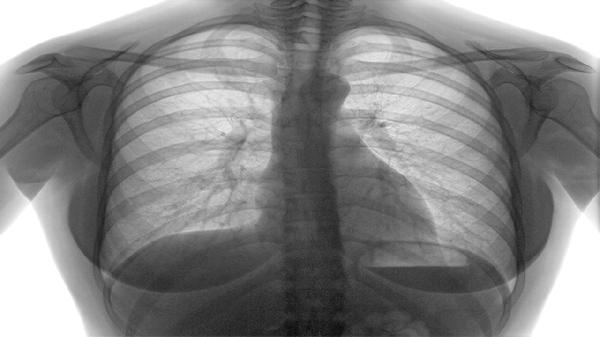

慢阻肺的首发症状通常是慢性咳嗽,伴随咳痰,四大典型症状表现为慢性咳嗽、咳痰、气短和喘息。慢阻肺全称为慢性阻塞性肺疾病,是一种以气流受限为特征的慢性炎症性疾病,主要与吸烟、空气污染等因素有关。